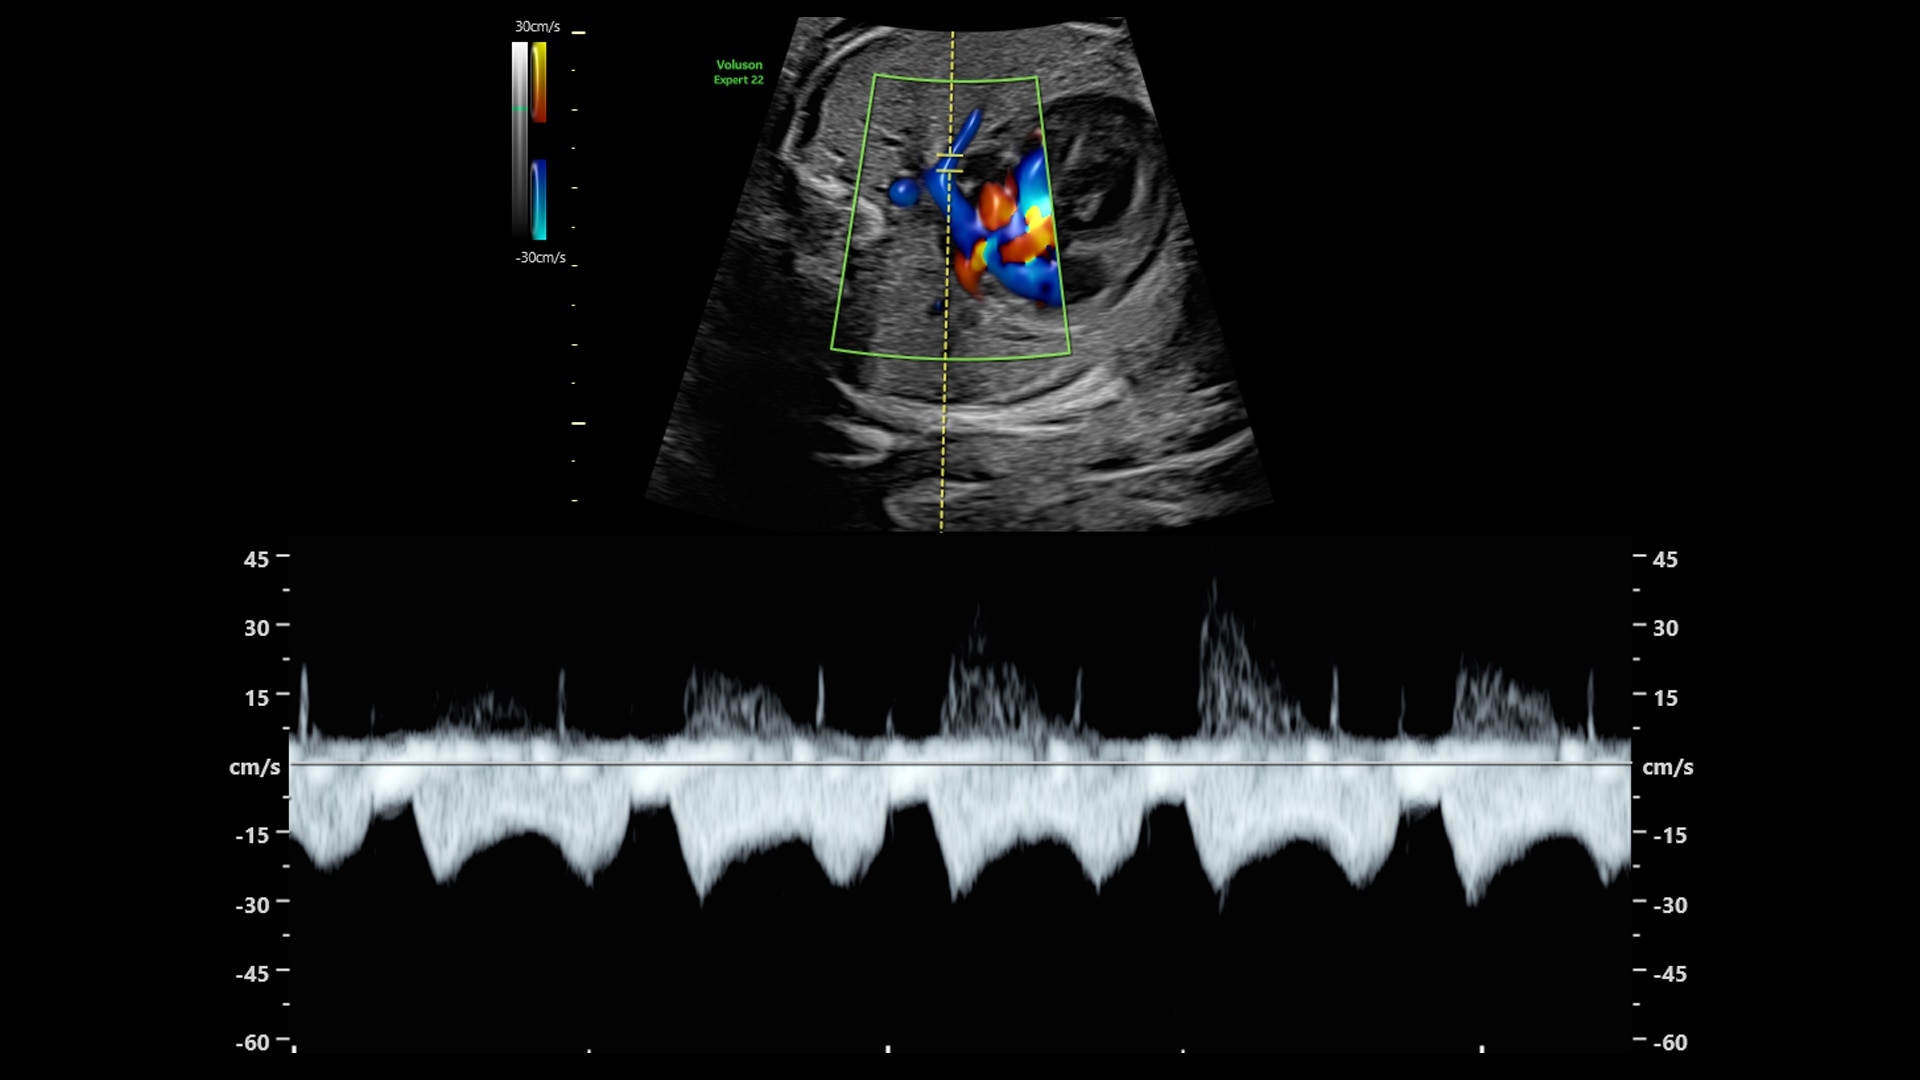

Doppler imaging

Beyond Basic Blood Flow

Voluson is pushing imaging boundaries to make blood flow assessment faster and easier. Our advanced technologies, including Graphicflow, Radiantflow, Slowflow, and Radiant imaging, increase resolution and sensitivity in color and pulsed wave Doppler for unprecedented clarity

Graphicflow

Hemodynamic Visualization

Provides a graphical representation of the trajectories of the blood cells in real-time to visualize complex blood flow quickly and clearly, helping you to differentiate normal from abnormal hemodynamics